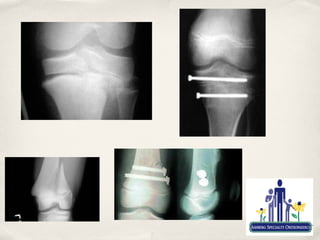

Fractures

Tibial Eminence fractures

✤   ACL equivalent in pre-adolescent child

✤   Most common in children 8-14 years old

✤   3 types-Meyers and Mckeever

✤   Type I-II usually amenable to cast immobilisation

✤   Type III always operative

✤   Not uncommon to have residual, post fixation laxity on objective testing

✤   Indicates ACL “stretch”

✤   Usually not clinically significant

✤   Tibial Tubercle and Patella Sleeve Fractures

✤   Mostly sports related

✤   Typically occur between 12-17 y/o

✤   Usually secondary to violent contraction of quad

✤   eg. Landing a jump

✤   At tubercle, fracture occurs at junction of ossified and cartilage growth plate

✤   Sleeve fractures occur because of cartilagenous attachment at inferior pole of

the patella

✤   Difficult to diagnose, but can result in complete disruption of extensor

mechanism.

Fractures ✤ Distal Femoral and Proximal Tibial Physeal fractures ✤ Most common fractures mistaken for ligament injury ✤ Need a high index of suspicion ✤ Treat as such until proven otherwise ✤ Can be most devastating to growth and life/limb ✤ Non-displaced fractures can usually be treated in a cast ✤ Displaced or intrarticular fractures frequently require surgery

Fractures Tibial Eminence fractures ✤ ACL equivalent in pre-adolescent child ✤ Most common in children 8-14 years old ✤ 3 types-Meyers and Mckeever ✤ Type I-II usually amenable to cast immobilisation ✤ Type III always operative ✤ Not uncommon to have residual, post fixation laxity on objective testing ✤ Indicates ACL “stretch” ✤ Usually not clinically significant

Fractures ✤ Tibial Tubercle and Patella Sleeve Fractures ✤ Mostly sports related ✤ Typically occur between 12-17 y/o ✤ Usually secondary to violent contraction of quad ✤ eg. Landing a jump ✤ At tubercle, fracture occurs at junction of ossified and cartilage growth plate ✤ Sleeve fractures occur because of cartilagenous attachment at inferior pole of the patella ✤ Difficult to diagnose, but can result in complete disruption of extensor mechanism.